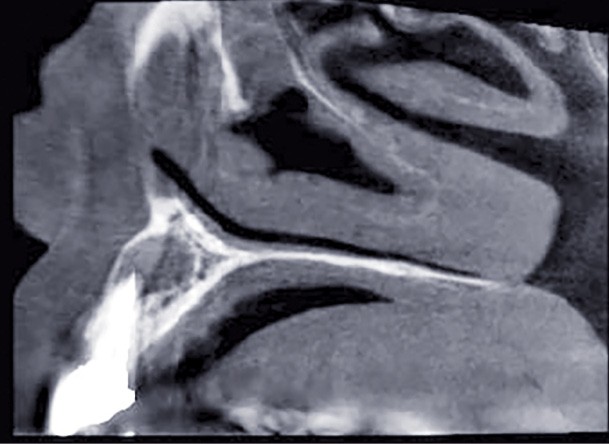

Examen radiographique

L’examen…